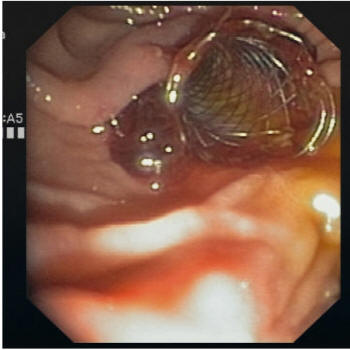

Photos of Heart Valve Bleeding

Images of Heart Valve Bleeding

Heart Valve Bleeding Pictures

Pictures of Heart Valve Bleeding

Heart Valve Bleeding Photos